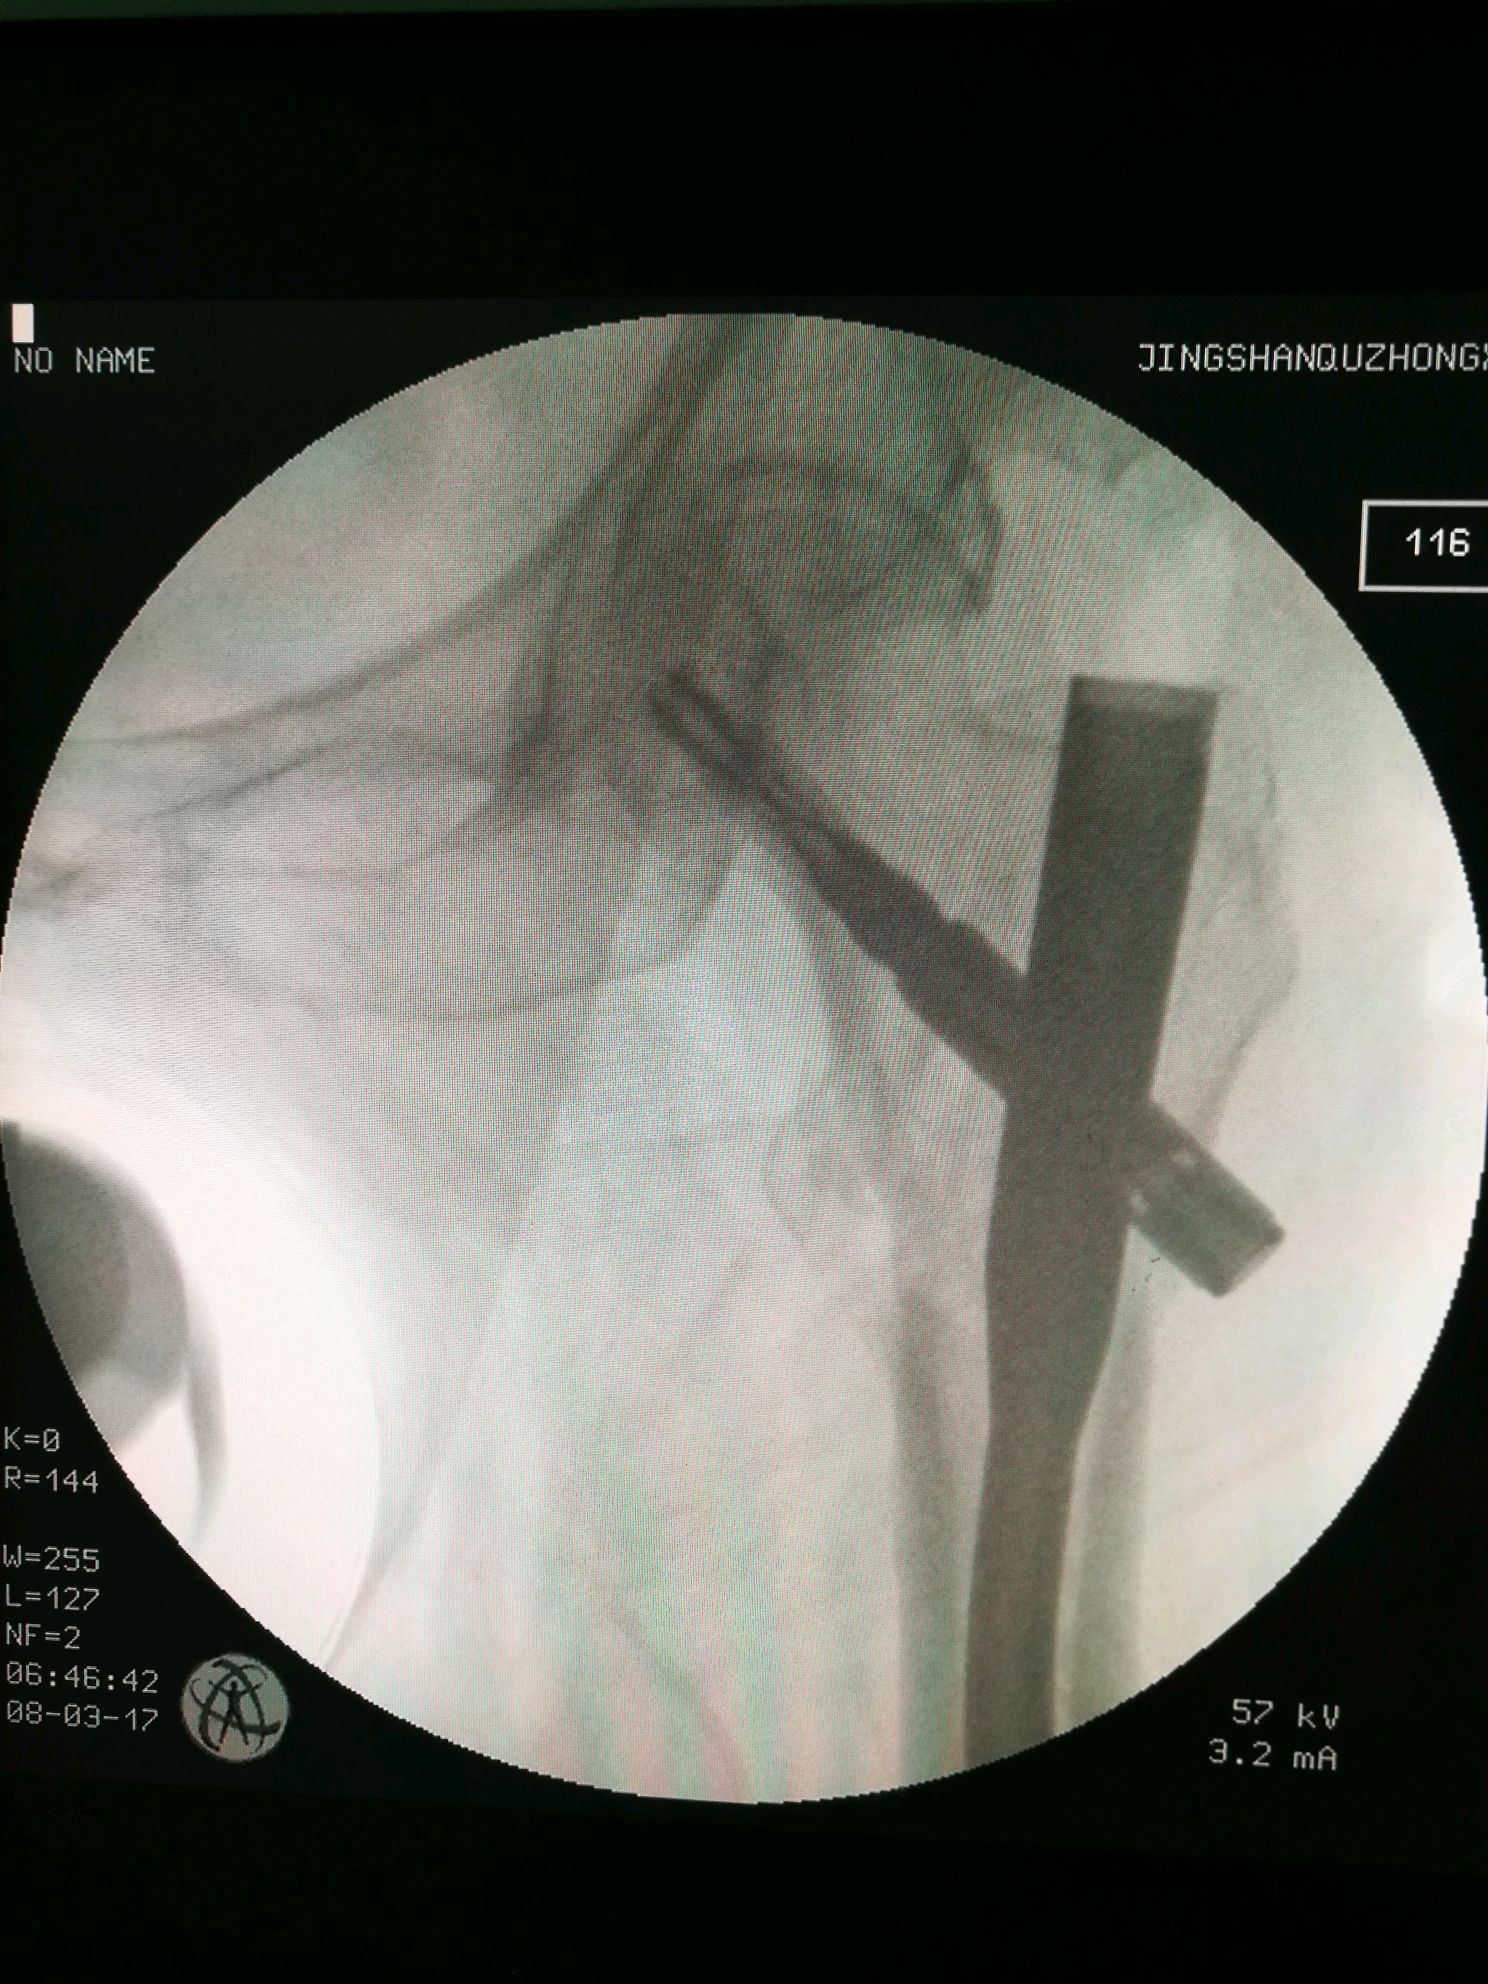

再来一例转子下骨折

图片尺寸1040x780